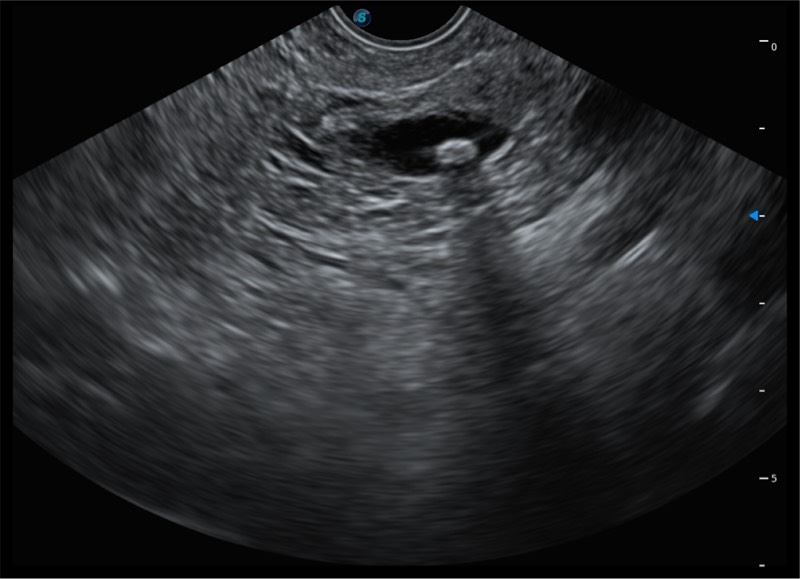

• 搭载百万级CMOS成像技术

• 及自主研发凸阵换能器,

• 可呈现优质的内镜和超声画面

• 4.0mm大钳道

• 12.6mm先端部外径

• 150°超声扫描角度

• 4-12MHZ宽频输出